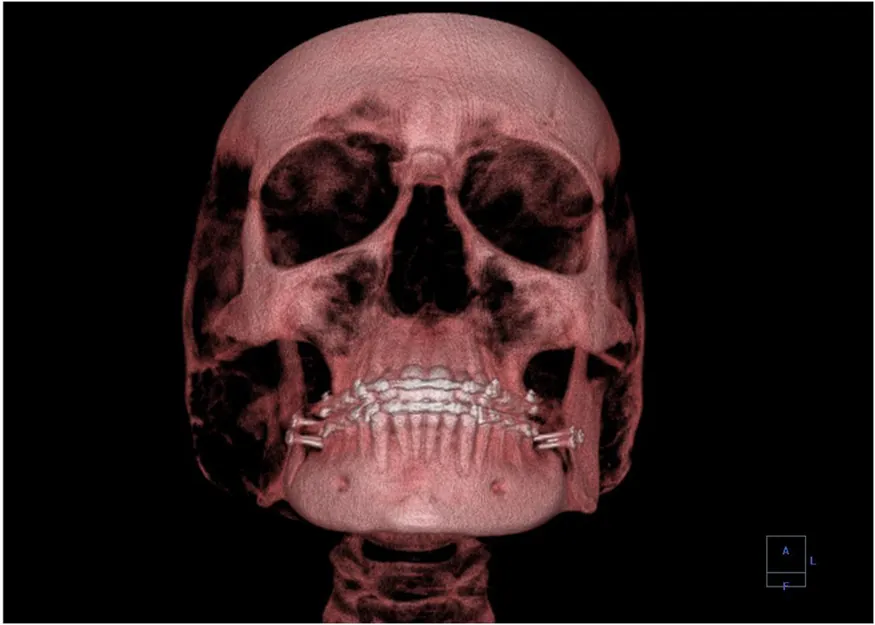

A 3-D image showing a human skull from the front.

Figure 30.28 This three-dimensional image of a skull was produced by computed tomography, involving analysis of several x-ray slices of the head. (credit: Emailshankar, Wikimedia Commons)

A standard x ray gives only a two-dimensional view of the object. Dense bones might hide images of soft tissue or organs. If you took another x ray from the side of the person (the first one being from the front), you would gain additional information. While shadow images are sufficient in many applications, far more sophisticated images can be produced with modern technology. Figure 30.27 shows the use of a computed tomography (CT) scanner, also called computed axial tomography (CAT) scanner. X rays are passed through a narrow section (called a slice) of the patient’s body (or body part) over a range of directions. An array of many detectors on the other side of the patient registers the x rays. The system is then rotated around the patient and another image is taken, and so on. The x-ray tube and detector array are mechanically attached and so rotate together. Complex computer image processing of the relative absorption of the x rays along different directions produces a highly-detailed image. Different slices are taken as the patient moves through the scanner on a table. Multiple images of different slices can also be computer analyzed to produce three-dimensional information, sometimes enhancing specific types of tissue, as shown in Figure 30.28. G. Hounsfield (UK) and A. Cormack (US) won the Nobel Prize in Medicine in 1979 for their development of computed tomography.